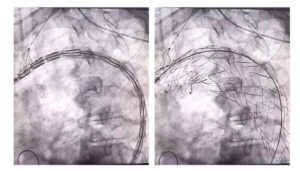

O paciente foi submetido a uma cirurgia minimante invasiva (pequeno corte na virilha) com utilização de endoprótese na aorta torácica para normalizar o fluxo de sangue e evitar o agravamento do aneurisma. A cirurgia com uso da prótese ramificada foi feita na unidade de Hemodinâmica da Santa Casa de Itabuna, por uma equipe comandada pelos médicos Luiz Felipe Brandão e André Brito, cirurgiões vasculares e endovasculares.

O procedimento inédito na Bahia durou 1h30min e 36 horas depois o paciente recebeu alta médica. “Isso ocorreu por trata-se de uma cirurgia minimamente invasiva, pois o abdômen ou o tórax do doente não são abertos. Por meio de uma incisão ou punção na artéria da virilha, utilizando fios e cateteres, coloca-se a endoprótese (rede metálica revestida por tecido)”, explica o médico Luiz Felipe Brandão.